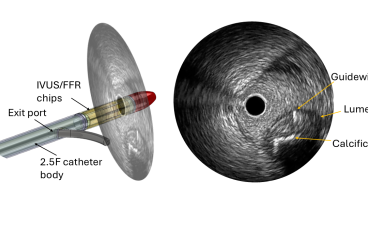

Blank Space (small)(text and background only visible when logged in) Articles Image Featured Woodruff School’s Mechanical Engineering Graduate Program Reaches Historic No. 3 Ranking By Ashley Ritchie Published: April 7, 2026 Read Article All News Category Sort by CategoryABabcontentAcoustics and Dynamicsadvisory boardAI and Informatics for MEAlumniASMEAutomation and MechatronicsAwardsBattery DayBioengineeringCAE and DesignCapstoneEngineering EducationEventsFacultyFluid MechanicsHeat Transfer, Combustion and Energy SystemsIntelligent SystemsManufacturingMEMechanics of MaterialsMedical PhysicsMicro and Nano EngineeringNRENREMPNuclear & Radiological EngineeringRankingsResearchRoboticsSCCStaffStudent Competition CenterStudentsTransportationTribology ImageME, NRE, NREMP, StudentsFrom Johannesburg to Georgia Tech: Johan Gouws Finds His Path in Nuclear Engineering ImageME, Research, Micro and Nano EngineeringTech Engineers to Develop a New Catheter to Improve Heart Procedures ImageME, Students, Capstone, NRE, NREMPWoodruff School Teams Shine at Spring 2026 Capstone Design Expo ImageME, NRE, Capstone, Students, NREMPProtecting Organs, Water, and the Military Earn Top Honors at Capstone Expo ImageME, Faculty, Research, Awards, BioengineeringAndrés García Elected to American Academy of Arts and Sciences ImageME, StudentsSpring 2026 ME 2110 Design Competition Takes Students Across the Galaxy ImageME, Research, Fluid MechanicsDoing the Dirty Work of Sustainability ImageME, NRE, NREMP, Alumni, AwardsWoodruff School Graduates, Faculty Honored with 2026 CoE Alumni Awards ImageME, ResearchGeorgia Tech Hosts Third Annual Crane Safety Research Center Meeting ImageME, Students, Faculty, Student Competition CenterGeorgia Tech Selected for Upcoming EcoCAR Challenge ImageME, Students, AwardsGeorgia Tech Celebrates Three Goldwater Scholars for 2026 ImageME, NRE, NREMP, Faculty, AwardsAnna Erickson Wins 2026 Corones Award for Research and Societal Impact Pagination Current page 1 Page 2 Page 3 Page 4 … Next page Last page Last